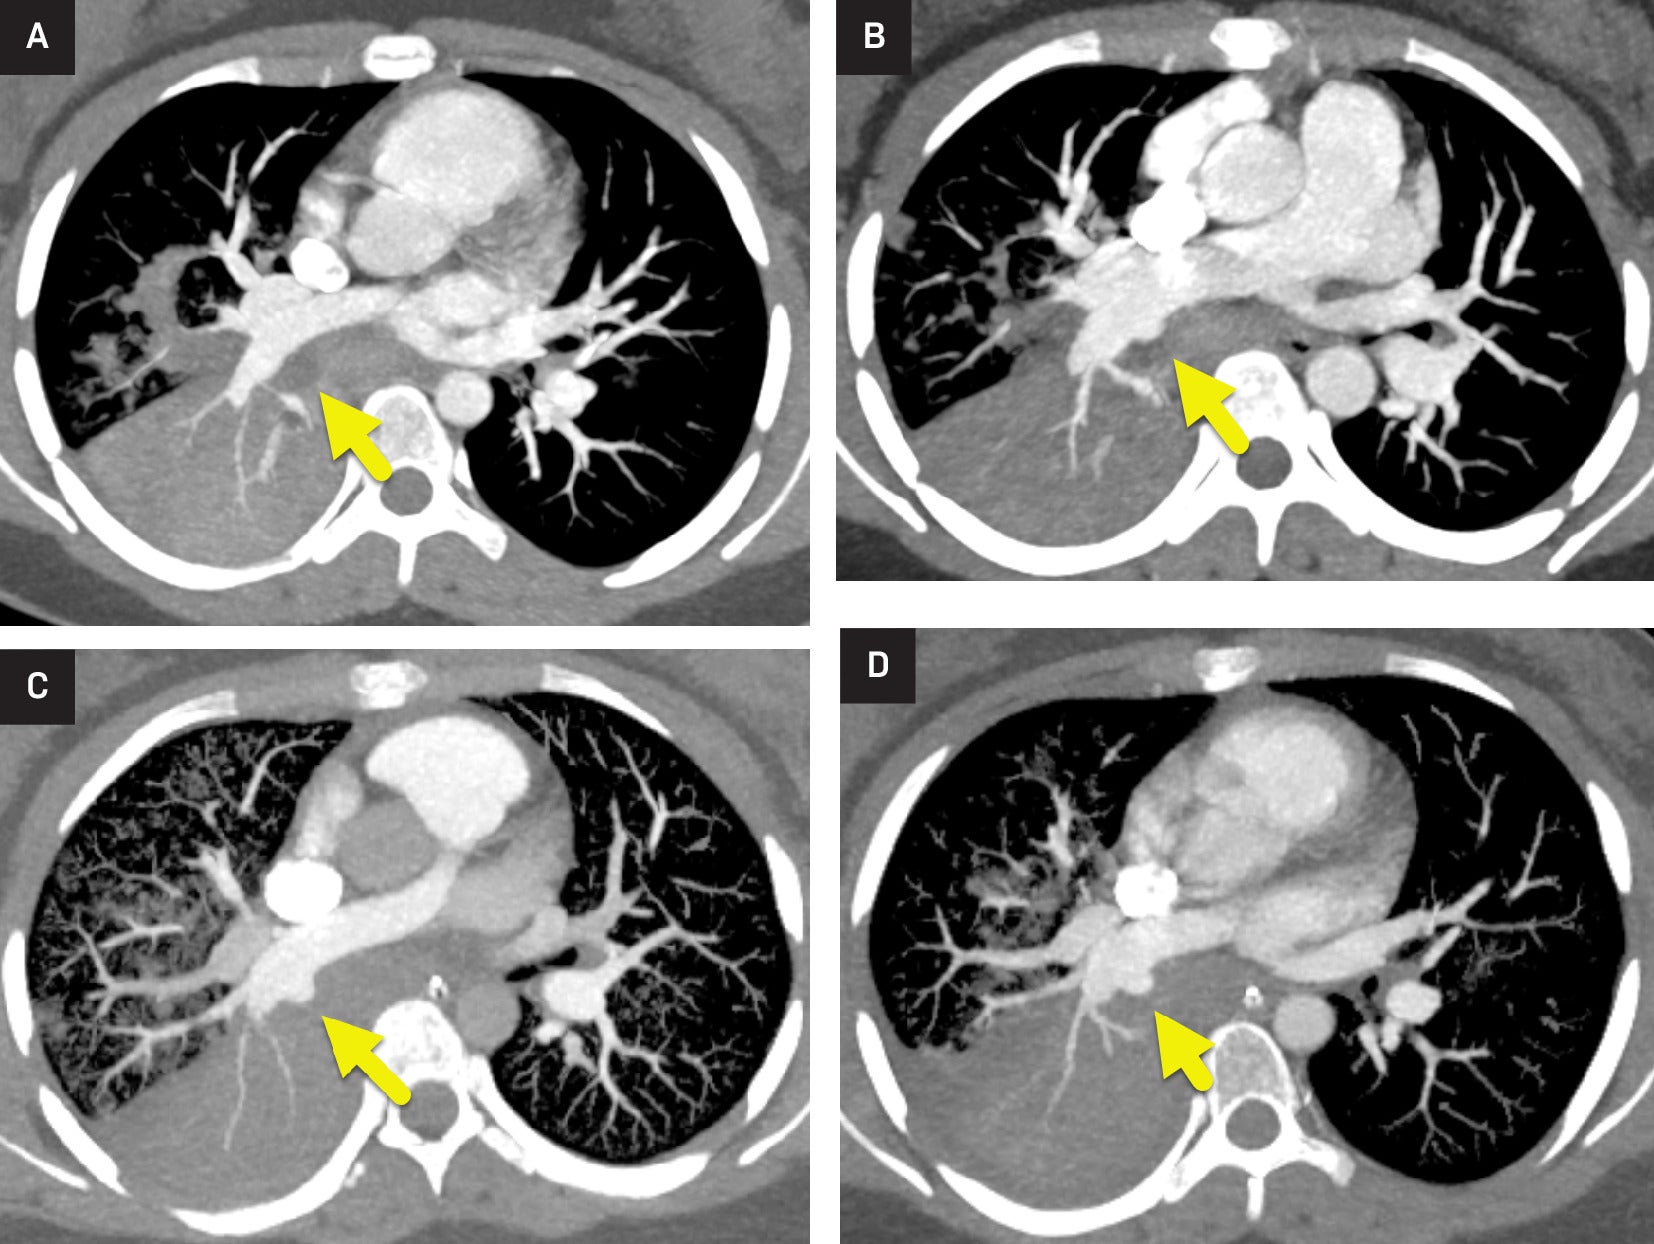

Pulmonary Artery Pseudoaneurysm